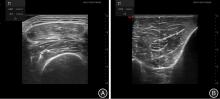

目的 探索股直肌横截面积(rectus femoris cross-sectional area, RF-CSA)、胫骨前肌厚度(tibialis anterior muscle thickness, TA-MT),以及生物电阻抗分析(bioelectrical-impedance-analysis, BIA)中的微观指标在重症监护室获得性衰弱(intensive care unit-acquired weakness, ICU-AW)中的诊断价值。 方法 对罹患肿瘤因脓毒症、脓毒症休克而进入天津医科大学肿瘤医院ICU的116例患者进行了一项单中心、观察性研究。通过患者的一般临床资料,并应用超声和生物电阻抗分析检测脓毒症发生6 h以内以及脓毒症治疗72 h以后股直肌、胫骨前肌、骨骼肌指数(SMI)、全身水含量(TBW)、蛋白质含量(Protein)等指标的变化,并进行统计学分析来预测ICU-AW的发生概率。 结果 最终41例患者诊断为ICU-AW,ICU-AW患者中存在更高比例的血管活性药物使用、机械辅助通气治疗,而且急性生理学和慢性健康状况评价Ⅱ(APACHEⅡ)和SOFA评分更高,病情更危重。另外分组对比显示ICU-AW组的患者在股直肌横截面积(RF-CSA)、胫骨前肌厚度(TA-MT)、骨骼肌指数(SMI)、全身水(TBW)、蛋白质含量(Protein)方面下降程度更为显著(P < 0.05)。此外,相比No ICU-AW组患者,在ICU-AW组患者中,初始平均PA值更低(3.42° vs. 3.80°),通过积极治疗后PA上升趋势更高。在ICU-AW诊断方面发现RF-CSA、TA-MT、SMI、TBW、Protein变化率在诊断ICU-AW上显示出较高的ROC-AUC[分别为0.891(95%CI为0.831 ~ 0.952),0.830(95%CI为0.749 ~ 0.911),0.916(95%CI为0.862 ~ 0.971),0.833(95%CI为0.749 ~ 0.917),0.834(95%CI为0.758 ~ 0.911)],此外,初始APACHEⅡ评分也显示出良好的诊断价值,ROC-AUC为0.829(95%CI为0.803 ~ 0.917),联合诊断模型中,生物电阻抗分析所测量的SMI变化率和Protein变化率联合模型具有最高的ROC-AUC(0.938,95%CI为0.895 ~ 0.980)。 结论 肿瘤脓毒症患者外周肌肉超声检测和生物电阻抗分析可以作为早期识别ICU-AW的方式。

Objective To explore the application of rectus femoris cross-sectional area (RF-CSA), Tibialis anterior muscle thickness (TA-MT), and bioelectrical-impedance-analysis (BIA) in the diagnosis of intensive care unit-acquired weakness (ICU-AW). Methods A single-centre, observational study was carried out on 116 patients who were admitted to the Intensive Care Unit (ICU) of Tianjin Medical University Cancer Hospital because of tumour-related sepsis or septic shock. By examining the patients' general clinical data and using ultrasound and bioimpedance analysis to monitor the changes in indicators such as rectus femoris, tibialis anterior, skeletal muscle index (SMI), total body water (TBW), and protein content within 6 hours after the onset of sepsis and 72 hours after the initiation of sepsis treatment, statistical analysis was performed to predict the probability of ICU-AW occurrence. Results Ultimately, a total of 41 patients were diagnosed with ICU-AW. Patients with ICU-AW had a higher proportion of vasoactive drug use and mechanical ventilation, along with elevated Acute Physiology and Chronic Health Evaluation Ⅱ (APACHE Ⅱ) and Sequential Organ Failure Assessment (SOFA) scores, which clearly indicated a more severe state of illness. Moreover, group-by-group comparisons showed more significant decreases in RF-CSA, TA-MT, SMI, TBW, and protein content (Protein) in the ICU-AW group (P < 0.05). In addition, compared to the non-ICU-AW group, ICU-AW patients had lower initial mean Passive Angle (PA) values (3.42° vs. 3.80°) and showed a more rapid increase in PA after aggressive intervention. When it came to the diagnosis of ICU-AW, the change rates of RF-CSA, TA-MT, SMI, TBW, and Protein presented higher Receiver Operating Characteristic-Area Under the Curve (ROC-AUC) values for diagnosing ICU-AW [0.891 (95%CI: 0.831 ~ 0.952), 0.830 (95%CI: 0.749 ~ 0.911), 0.916 (95%CI: 0.862 ~ 0.971), 0.833 (95%CI: 0.749 ~ 0.917), and 0.834 (95%CI: 0.758 ~ 0.911), respectively]. Furthermore, the initial APACHE Ⅱ score showed good diagnostic value, with a ROC-AUC of 0.829 (95%CI: 0.803 ~ 0.917). In the combined diagnostic model, the joint model that included the SMI change rate and Protein change rate measured by bioimpedance analysis achieved the highest ROC-AUC (0.938, 95%CI 0.895 ~ 0.980). Conclusion Peripheral muscle ultrasound and bioelectrical impedance analysis can be employed as effective tools for the early detection of ICU-AW in patients with tumor sepsis.